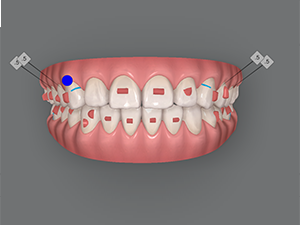

Kết quả đạt được

- Đạt tương quan khớp cắn loại I

- Đạt overjet và overbite bình thường

- Cải thiện overjet

- Đạt đường cười thẩm mỹ

- Tương quan răng cối và răng nanh đã được điều chỉnh

- Đạt tương quan overjet và overbite bình thường

- Cắn hở vùng răng trước được điều trị bằng intrusion răng sau và extrusion răng trước